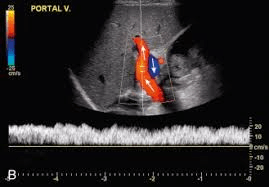

Normal flow of the portal vein is hepato_____.

Hepatopetal

Hepatopetal means TOWARD the liver. Normally high-volume portal venous flow is characterized by minimally phasic, slightly disordered flow with low peak and mean velocities. It normally accelerates during expiration and deaccelerates during inhalation.